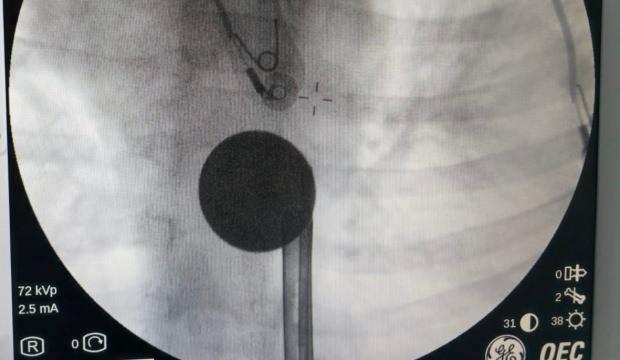

Siirt'te 8 yaşındaki çocuğun boğazına madeni 5 lira kaçtı. Hastaneye götürülen çocuğu doktorların titiz çalışması kurtardı.

Paylaşılan bilgilere göre 8 yaşındaki Y.K., yabancı cisim yutma şikayetiyle ailesi tarafından Siirt Eğitim ve Araştırma Hastanesine götürüldü.

Yapılan ilk değerlendirme ve görüntüleme tetkiklerinin ardından çocuk, ilgili branşlar tarafından operasyona alındı.

Y.K.'nın yemek borusuna kadar ilerlediği tespit edilen madeni para, gastroenteroloji uzmanı Dr. Yaren Dirik ve kulak burun boğaz hekimi Yasin Gökçınar tarafından müdahale edilerek çıkartıldı.

Operasyonun ardından bir süre gözlem altında tutulan Y.K., tedavisinin tamamlanmasıyla taburcu edildi.

"Hastanemize başvuran 8 yaşındaki hastamızın yemek borusuna kaçan madeni para, gastroenteroloji ve KBB ekiplerimizin koordineli ve titiz çalışmasıyla herhangi bir komplikasyona yol açmadan başarılı bir şekilde çıkarılmıştır. Operasyon süreci sorunsuz geçmiş olup hastamızın genel durumu iyidir."